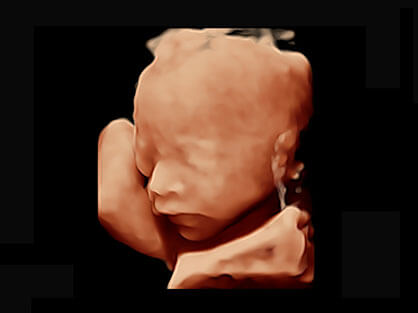

作为P系列家族成员之一,P40 Plus采用诸侯快讯官网高端超声系统平台——极光,并以时尚秀丽、小巧灵动的外观设计绽放出灵动之韵、科技之美。高端平台的使用保证了P40 Plus优质的基础图像;完备的高级功能可满足您全身应用的基本需求;丰富的探头配置、多样的高级4D成像及分析软件为您日益增多的妇产应用需求提供丰富的诊疗方案。

宽频带腹部凸阵探头和腹部容积探头、大角度腔内探头和腔内容积探头、独特的生殖专用曲柄探头,为妇产应用提供全面诊疗方案。